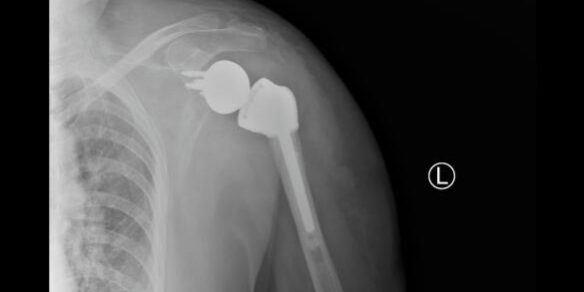

X光片顯示肩關(guān)節(jié)假體在位良好

術(shù)后患者狀況良好,第二天即可開始下地活動,肩關(guān)節(jié)也可以做一些簡單的前后運動,X光片顯示肩關(guān)節(jié)假體在位良好,目前患者已康復(fù)出院。